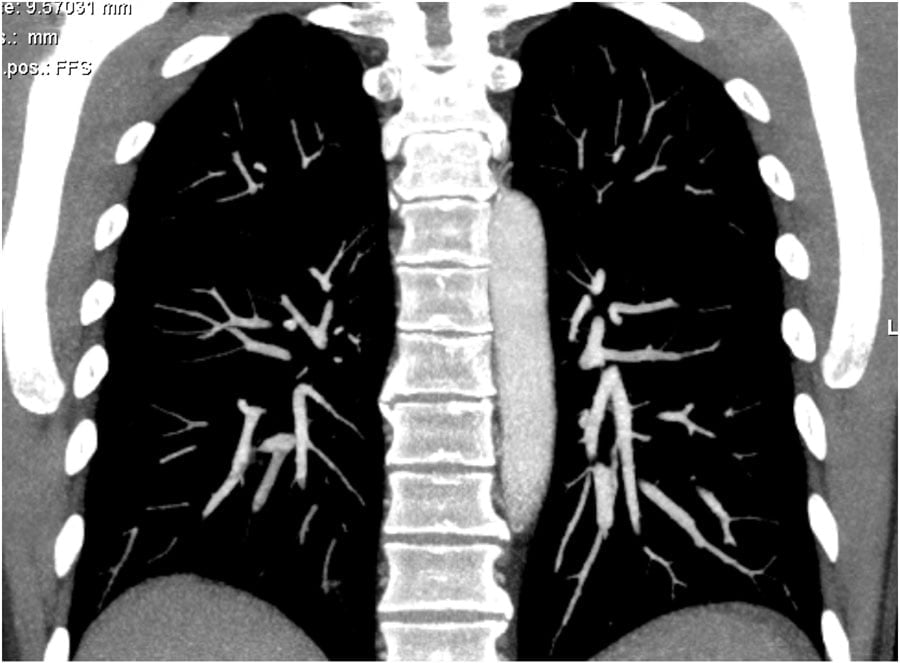

Thick MIP reconstructions can be helpful in following the vessels and detecting emboli.

Hình tái tạo MIP dày cho phép theo dõi và phát hiện thuyên tắc.